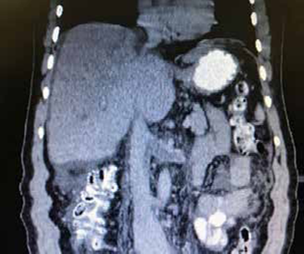

En la endoscopia de vías digestivas altas se observaron várices esofágicas de grado I-II y el ecocardiograma transtorácico fue normal. En la ecografía abdominal, se encontró abundante líquido ascítico libre, hipertrofia del lóbulo caudado, trombosis de las venas hepáticas y un sistema venoso portal normal. La tomografía computarizada abdominal demostró trombosis de la vena cava inferior, las venas hepáticas y la vena renal izquierda (figura 2).